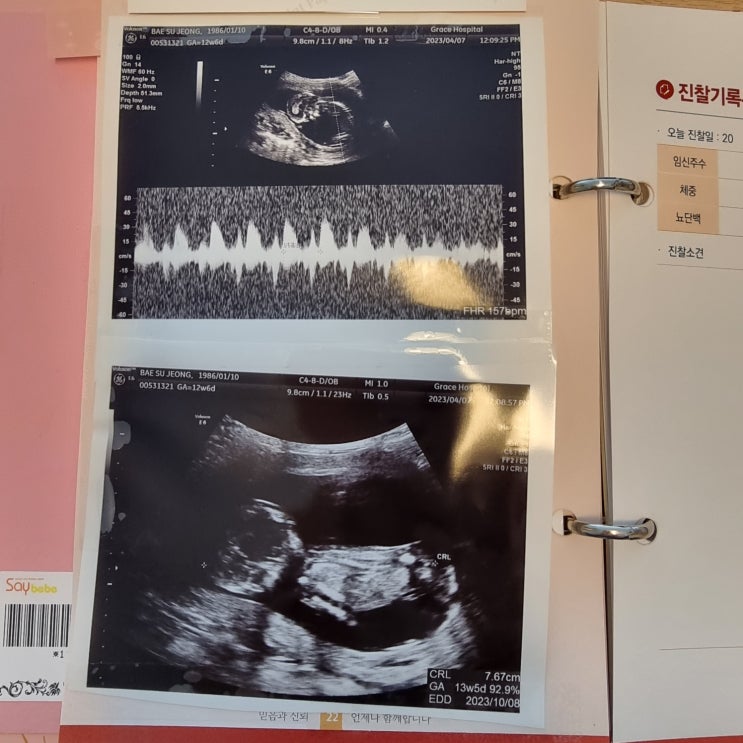

[임신9주~13주] 입덧끝, 성별O, 기형아검사, 산후조리원 비교, 임신소양증

입덧먹덧 완화 이제 배고프면 막 울렁거리고, 먹으면 목구멍에 뭐가 계속 얹혀있고 하는 먹덧증상이 거의 ...